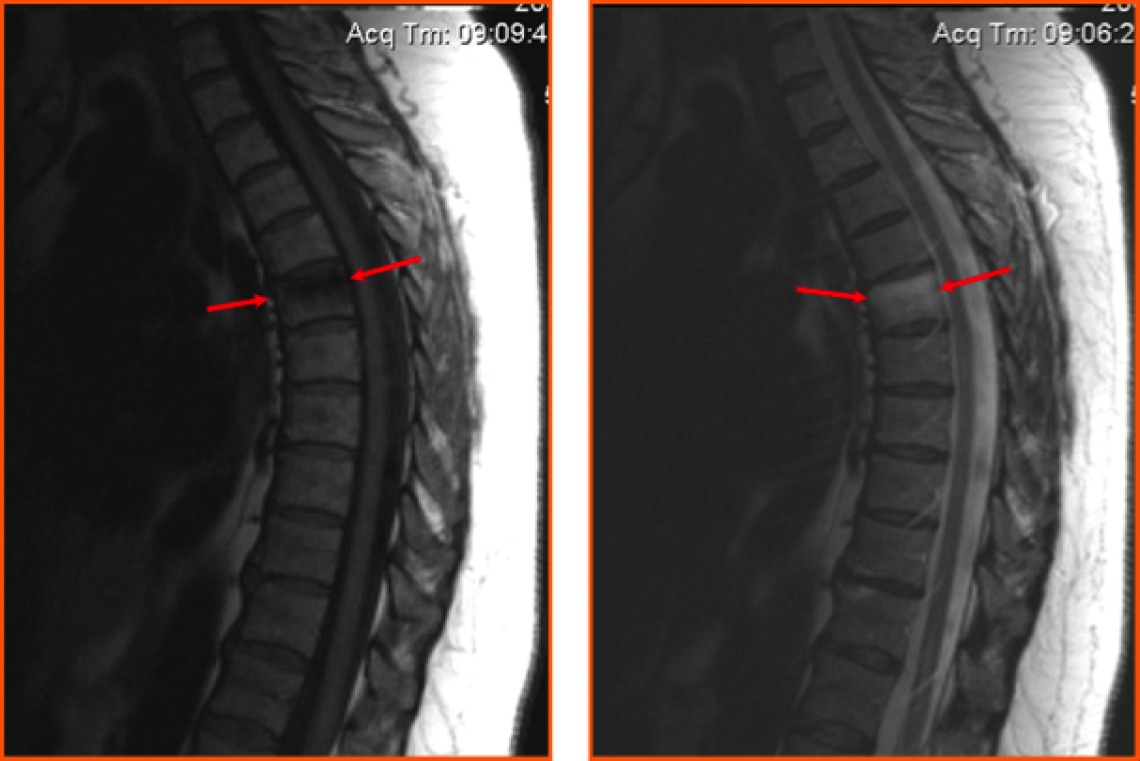

Для диагностики протрузии дисков грудного отдела используются магнитно-резонансная томография, ультразвуковое исследование и рентгенография.

Заболевание требует своевременной и точной диагностики, так как лечение зависит от степени распространенности и типа поражения (срединная, боковая или срединно-боковая протрузия). Для оценки локализации и характеристик состояния назначается магнитно-резонансная томография (МРТ), которая является «золотым» стандартом в диагностике заболеваний позвоночника.

На основании полученных изображений специалисты могут установить:

- наличие трещин;

- степень выпячивания диска.